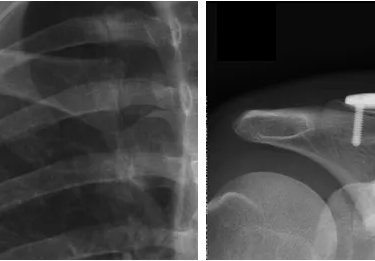

Fratura da Clavícula

A fratura da clavícula é frequente, e mais comum em crianças e adultos jovens. Pode ocorrer após traumas diretos na região, ou em quedas ao solo.